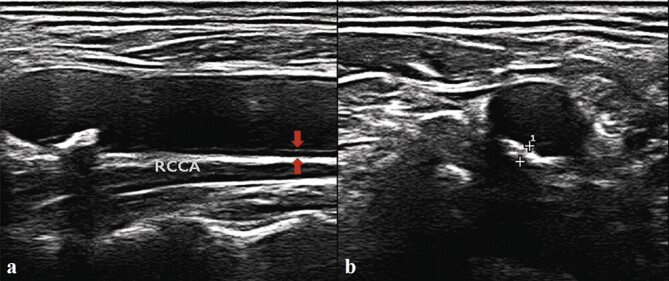

Purpose: Carotid ultrasound allows noninvasive assessment of vascular anatomy and function with real-time display. Based on the transfer learning method, a series of research results have been obtained on the optimal image recognition and analysis of static images. However, for carotid plaque recognition, there are high requirements for self-developed algorithms in real-time ultrasound detection. This study aims to establish an automatic recognition system, Be Easy to Use (BETU), for the real-time and synchronous diagnosis of carotid plaque from ultrasound videos based on an artificial neural network.

Materials and methods: 445 participants (mean age, 54.6±7.8 years; 227 men) were evaluated. Radiologists labeled a total of 3259 segmented ultrasound images from 445 videos with the diagnosis of carotid plaque, 2725 images were collected as a training dataset, and 554 images as a testing dataset. The automatic plaque recognition system BETU was established based on an artificial neural network, and remote application on a 5G environment was performed to test its diagnostic performance.